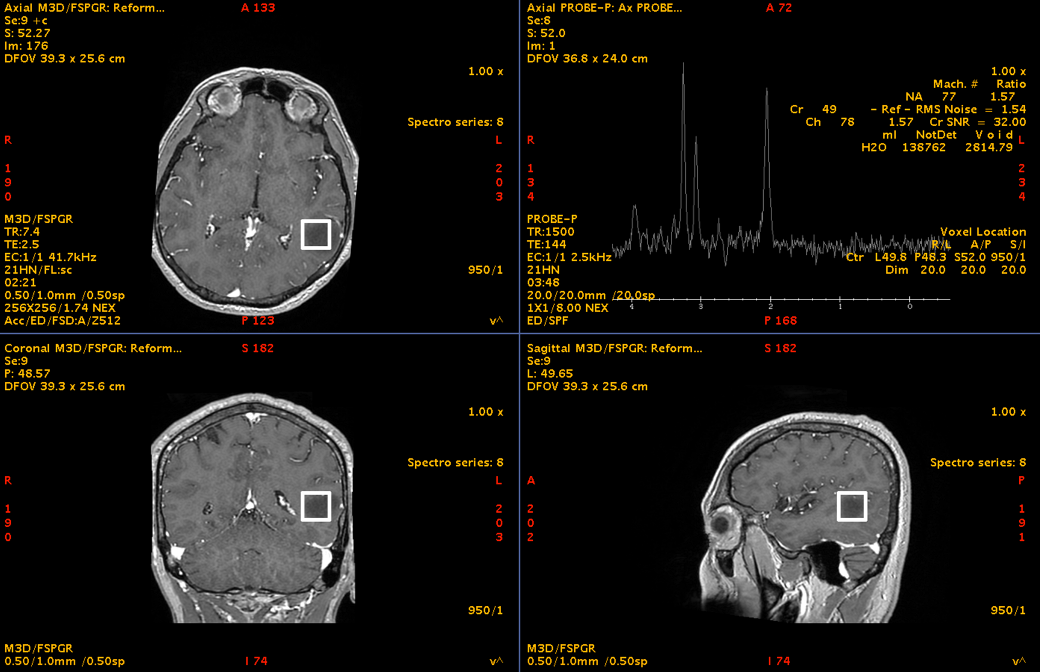

Spectroscopia RMN a susținut caracterul de proliferare tumorală glială, deși, așa cum se întâmplă frecvent în aceste leziuni, diagnosticul de certitudine nu putea fi stabilit doar imagistic, ci necesita confirmare histopatologică.

Dincolo de imagini, adevărata provocare era localizarea. Tumora se afla în lobul temporal stâng, în vecinătatea unor structuri esențiale pentru limbaj. Analiza preoperatorie a arătat că leziunea infiltra și limita fasciculele lungi de asociație din substanța albă profundă a emisferului stâng. La polul superior al regiunii tumorale se afla aria Wernicke, cu rol crucial în înțelegerea limbajului. În profunzime și în vecinătate erau implicate rețele funcționale majore, în special fasciculul arcuat stâng, cu rol central în limbaj, și fasciculul fronto-occipital inferior (IFOF), important pentru integrarea semantică și cognitivă, pentru înțelegerea complexă a limbajului, dar și pentru integrarea informației vizuale.